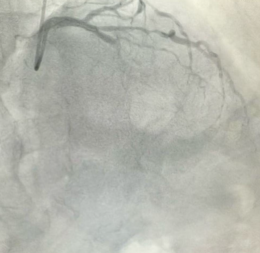

专业守护从“心”开始日照市康复医院心脏康复科今年73岁的于大爷(化名),半月前突发持续性胸痛被紧急送至我院急诊科。检查发现,于大爷患有急性广泛前壁心肌梗死,情况危急。既往有高血压病史4年,血压最高达1...